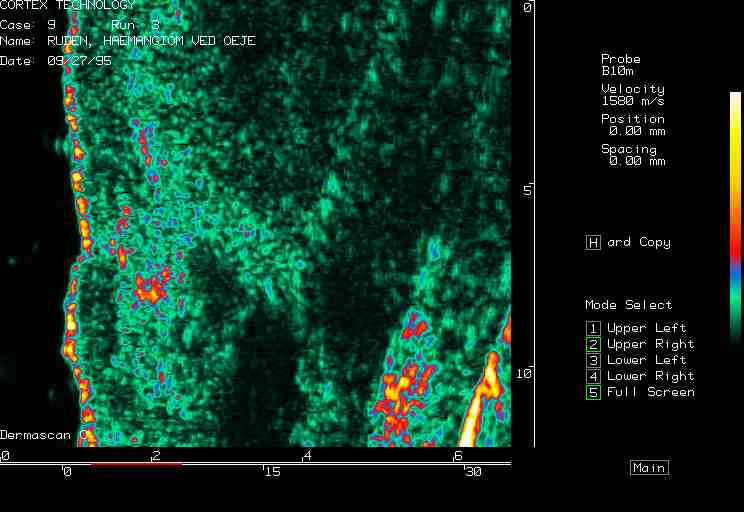

Hemangioma, nose |

Facial hemangioma 1 |

Facial hemangioma 2 |